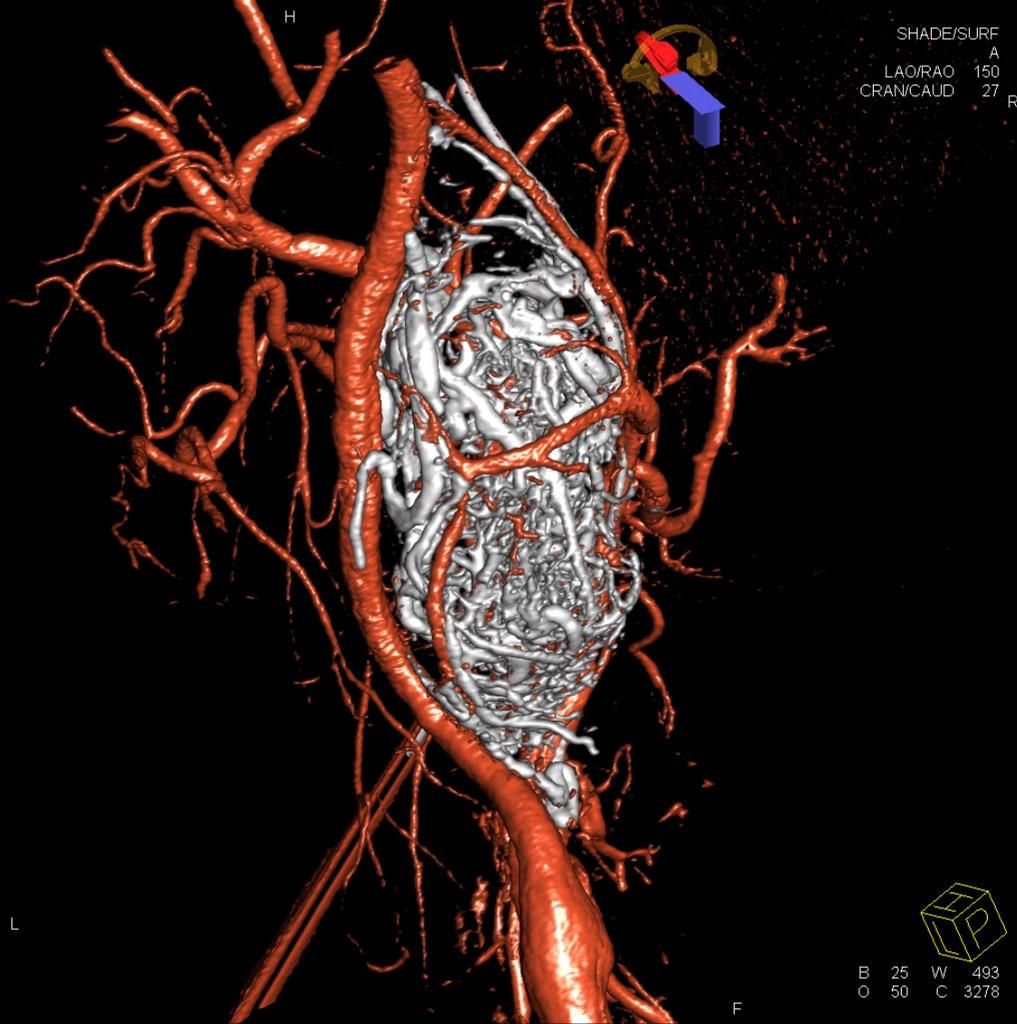

- Eco-Color-Doppler (ECD) dei tronchi sovra-aortici (TSA), ECD dell'aorta addominale e dei vasi iliaci, ECD aorto-iliaco, ECD celiaco-mesenterico, ECD degli arti inferiori arterioso o venoso, ECD degli arti superiori arterioso o venoso, ECD testicolare, ECD delle arterie temporali, ECD trans-cranico senza mdc.

- TC con o senza mezzo di contrasto (mdc): TC encefalo, TC cranio, TC massiccio-faciale, TC rocche e mastoidi, TC dell'orecchio, TC delle arcate dentarie (Dentalscan), TC dell’articolazione temporo-mandibolare (ATM), TC torace, TC addome, TC pelvi, TC articolare, TC della colonna vertebrale (cervicale, dorsale, lombare, lombo-sacrale), Angio-TC dell'encefalo e del Poligono di Willis, Angio-TC dei tronchi sovra-aortici, Angio-TC dell'aorta toracica e addominale, Angio-TC degli arti inferiori.